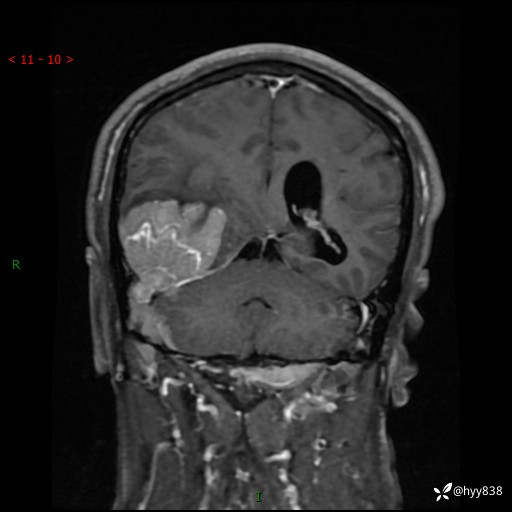

患者性别:男

患者年龄:56岁

简要病史:外院CT提示脑膜瘤,为进一步诊治来我院

辅助检查:MRI

临床诊断:颅脑占位

颅脑MRI平扫+增强

脑膜瘤 (78)

脑膜孤立性纤维性肿瘤/血管外皮瘤 (1)

单发性纤维性肿瘤 (39)